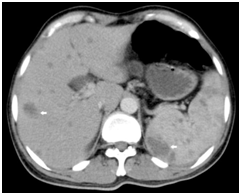

A 42-year old male with B-cell acute lymphoblastic leukemia on cytotoxic chemotherapy presented with high grade fever and fatigue. He had received daunorubicin, L-Asparaginase, vincristine and prednisolone as part of chemotherapy maintenance protocol 2-months back. In his last review 2-weeks back he had pancytopenia with an absolute neutrophil count of 200/mm3, but was asymptomatic. On examination he was febrile with a temperature of 1030F and was hemodynamically stable. Physical examination revealed severe pallor and mild hepatomegaly. Investigations showed a hemoglobin of 6.6g/dL, WBC count of 1600/mm3 with 44% polymorphs and 46% lymphocytes, neutrophil count of 700/mm3 and platelet count of 7000/mm3. His alkaline phosphatase was remarkably high with 345IU/L, while rest of the liver function tests were normal. Blood cultures were sterile. An ultrasound of the abdomen was normal. He was started on piperacillin-tazobactam and amikacin, but had little response. A computed tomography (CT) of the abdomen was done and showed numerous non-enhancing lesions in the liver and spleen with few of them showing conglomeration and subcapsular extension (Figure 1). A biopsy from the lesions was deferred due to thrombocytopenia. The clinical and radiological features were suggestive of hepatosplenic candidiasis. He was started on IV Amphotericin-B 50mg IV once daily and supported with blood transfusions. His fever subsided, alkaline phosphatase values returned to normal level and cytopenias resolved. He was later discharged on oral fluconazole.

Figure 1 Computed Tomography in Hepatosplenic Candidiasis. Axial contrast enhanced CT showing numerous non-enhancing hypodense lesions in the liver and spleen typical of hepatosplenic candidiasis (arrows).